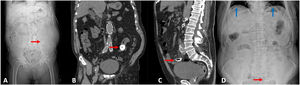

An 84-year-old man presented with abdominal pain, nausea, and vomiting. Abdomen X-Ray (image A) and CT scan (image B) revealed a 2.5 cm radiodense foreign body in the distal ileum (red arrows). Initially stable, he developed worsening abdominal pain, signs of peritonitis and septic shock three days later. Repeat imaging (images C and D) showed pneumoperitoneum (blue arrows). An exploratory laparotomy confirmed ileal perforation by a clam shell, requiring segmental enterectomy. He started piperacillin-tazobactam empirically. Peritoneal fluid culture isolated E. coli, and the antibiogram confirmed adequate coverage. In the postoperative course he required vasopressor support, developed transient respiratory failure requiring high-flow oxygen and experienced episodes of atrial fibrillation managed with amiodarone. Renal function gradually improved, and oral intake was reestablished. He stabilized hemodynamically, allowing transfer from Intensive Care to the Surgical ward. This case illustrates a rare cause of gastrointestinal perforation and septic shock due to accidental foreign body ingestion, underscoring the importance of early recognition and intervention in elderly patients with vague abdominal symptoms and high complication risk.